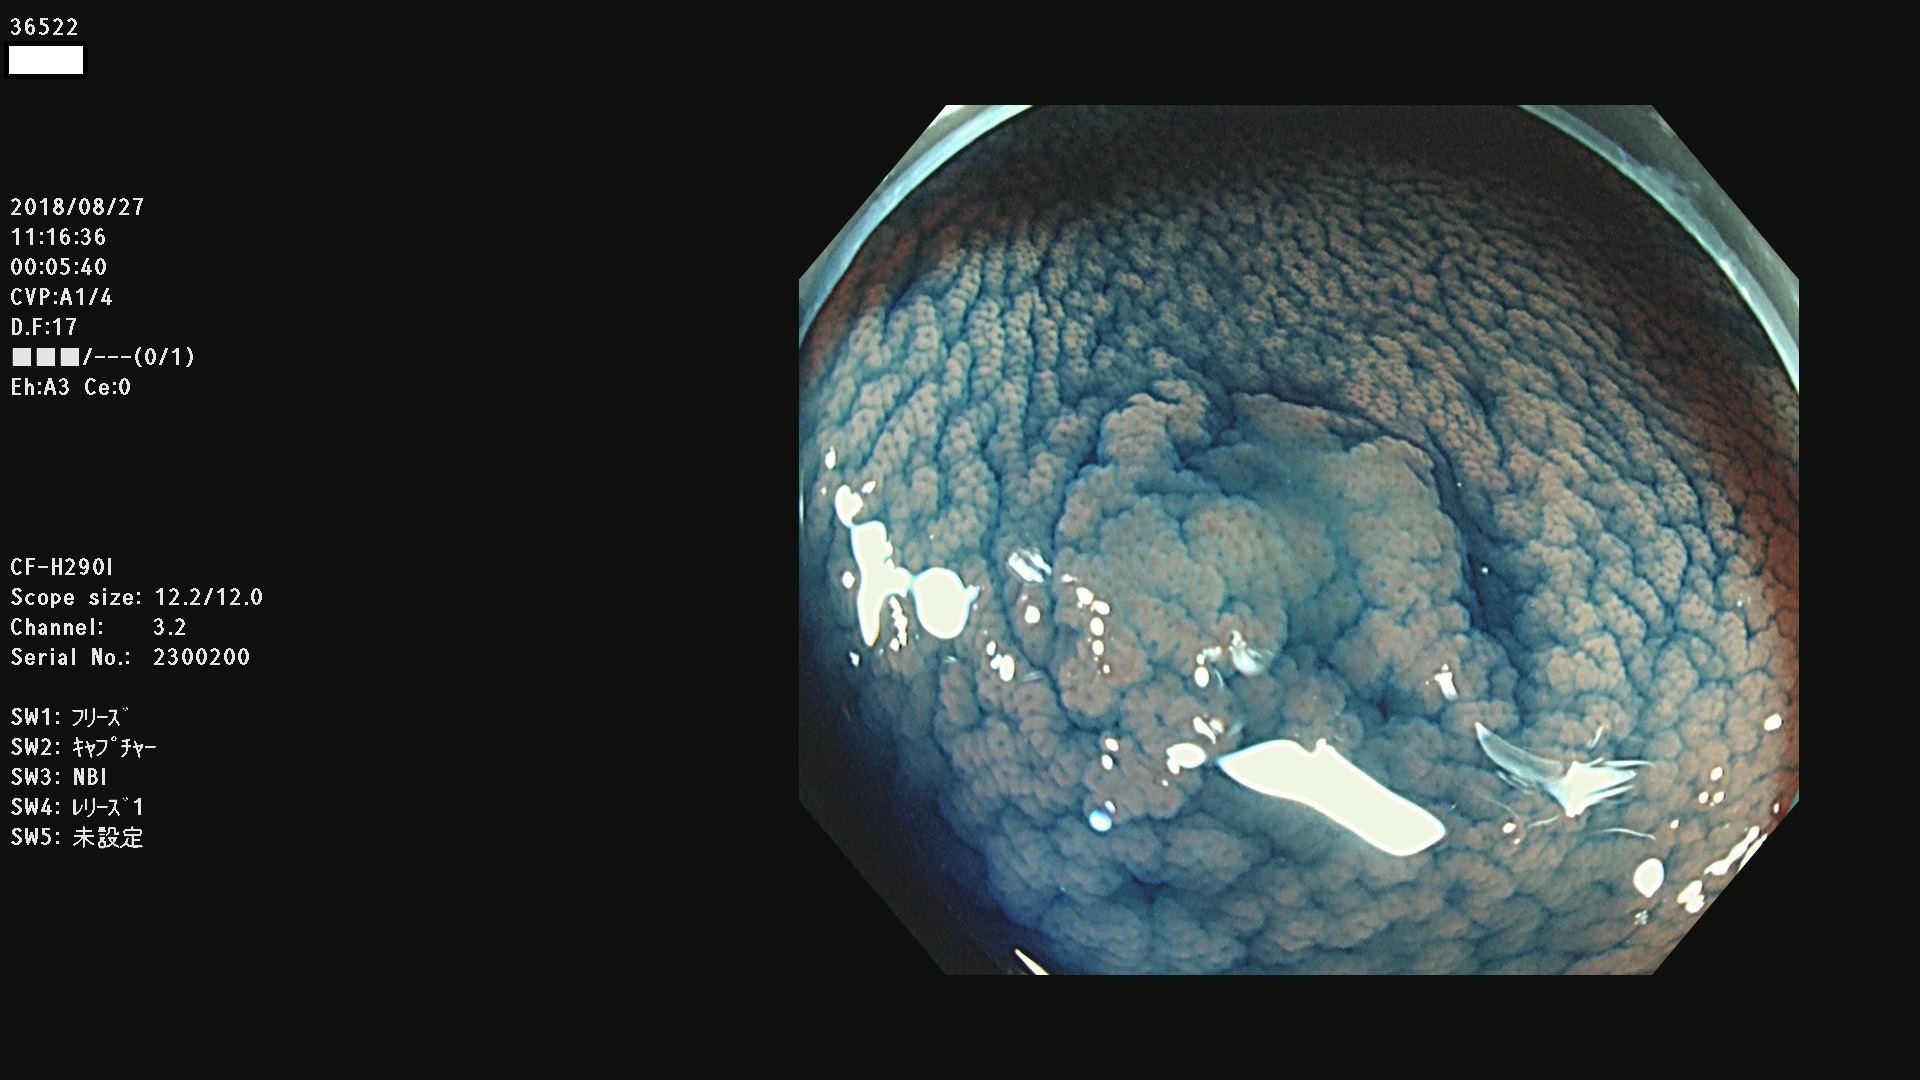

36500 36503 36504 36505 36507(SSAPのみ) 36508 36509 36510 36511 36514 36515 36517 36518 36520 36522(SSAPのみ) 36523 36524 36526 36528 36530 36531 36532 36533 36534 36535 36536 36538 36541 36542 36543 36544 36545 36546 36548 36550 36551 36554 36555 36556 36558 36559 36560 36561 36564 36565 36567 36568 36570 36572 36573 36574 36575 36576 36577 36578 36579 36580 36582 36584 36586 36591 36592 36593 36594 36595 36596 36597 36598

発見困難で危険性の高い平坦型病変(上記100名より抽出)

虫垂SSAP